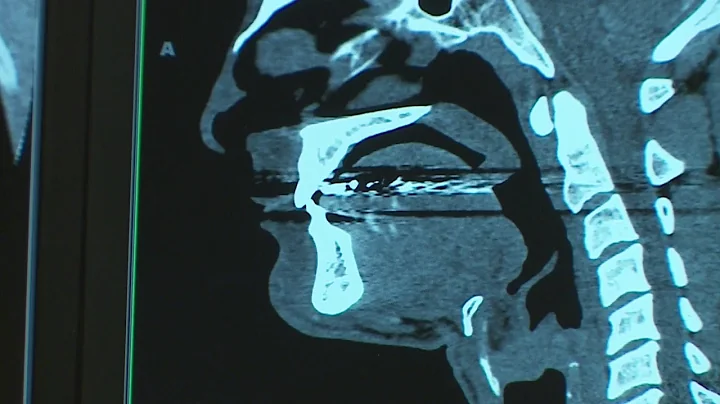

Brain Freeze Busters: The Neuroscience Of Ice Cream Headaches - Neuroscience News

Join us as we dive into the world of neuroscience to understand the sudden, intense headache we often experience while ...